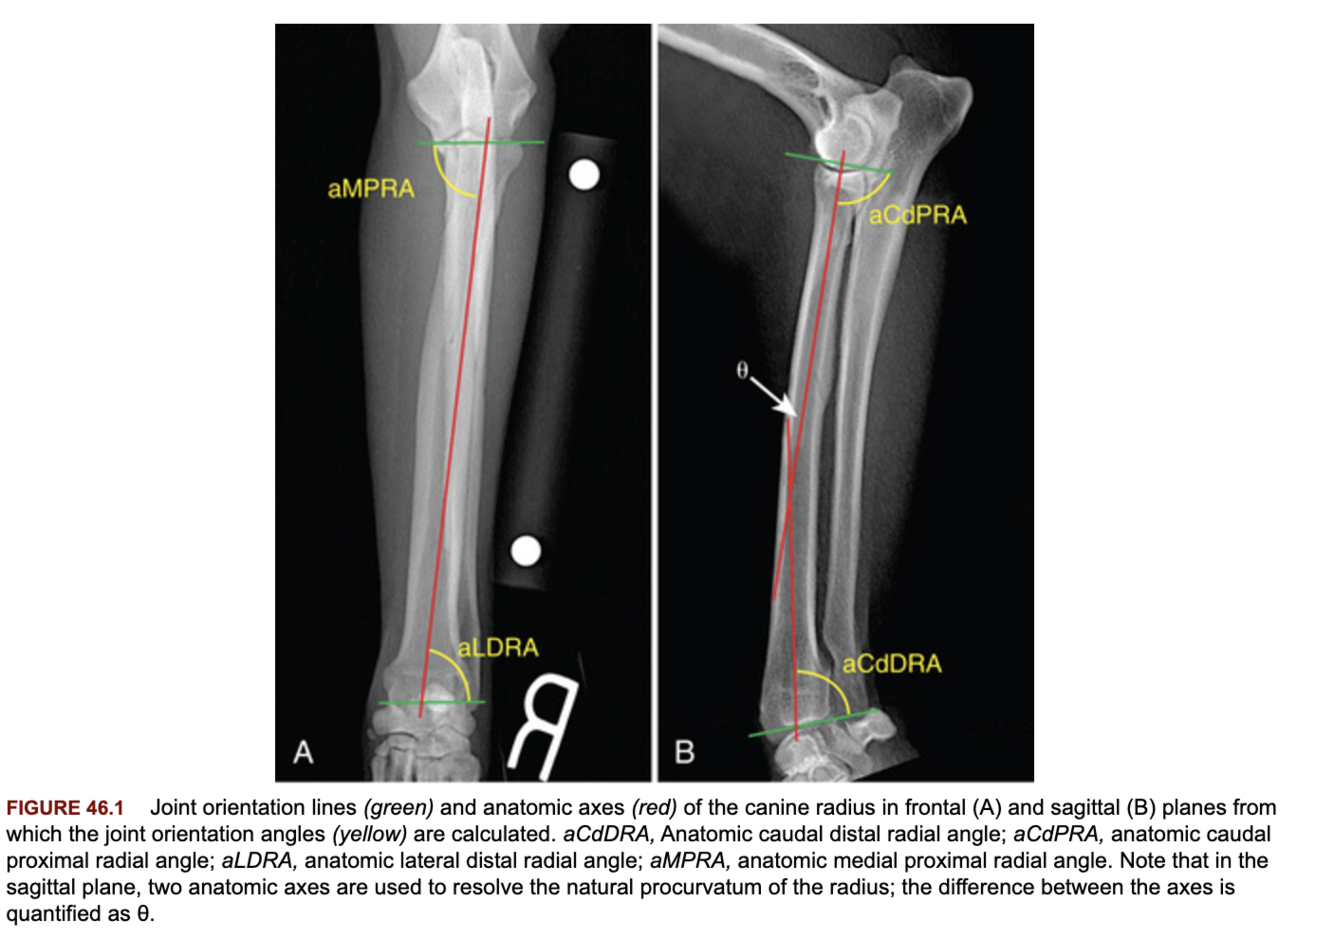

Describe the method of radiographic measurement of the joint orientation lines of the radius?

Frontal: from the radial head to the medial coronoid proximally, and the joint line ignoring the styloid process distally.

Sagittal: joint line proximally and distally.

Procurvatum is calculated using the following formula: (90 degrees − aCdPRA) + (90 degrees − aCdDRA) + θ